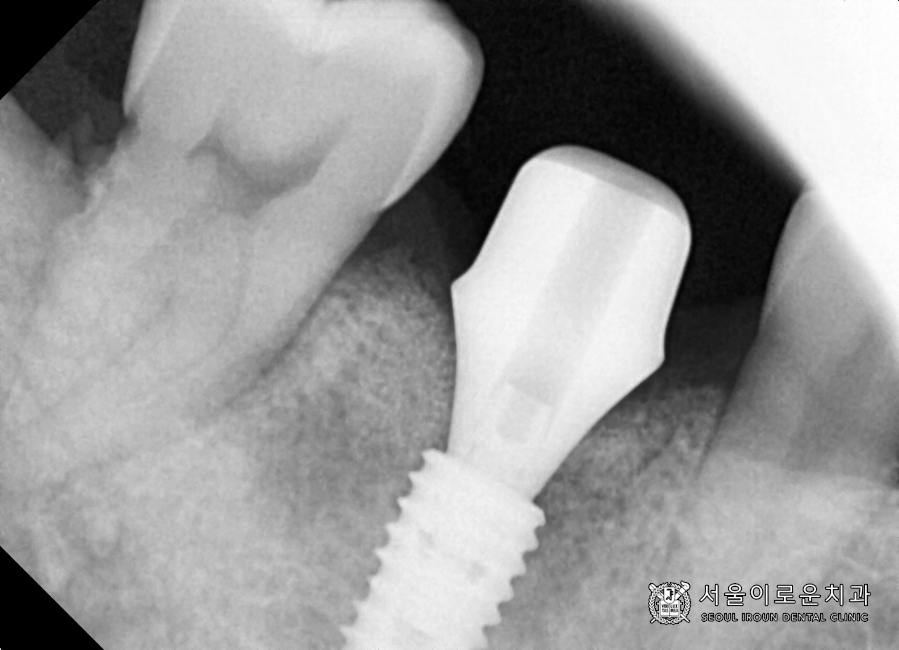

가장 먼저, 발치 후

염증조직을 깨끗이 제거한 뒤

뼈이식을 동반한 임플란트를 식립하였습니다!

* 염증조직이 남아 있을 경우,

뼈이식 뒤 골유착에 방해를 줄 수 있어

사전에 말끔히 제거하는 것이

필요합니다.

2달반 후

뼈와 임플란트가 잘 붙었는지 확인하는

osstell beacon이라는 장비를 이용하여

isq(골유착정도)를 측정하였는데요.

안정적이라는 것을 확인하고

오른쪽 아래 첫번째 큰 어금니(#46)에

성공적으로 보철과정을

마무리 하였습니다. 😄